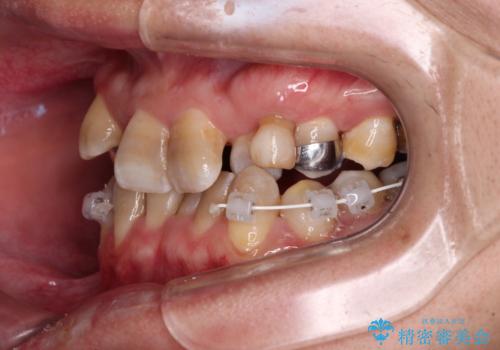

それらを改善するため上顎に拡大装置を用いて、審美装置にてワイヤー矯正を行いました。

左上の乳犬歯は当初保存する計画でしたが、虫歯が大きいため抜歯になり、患者様の希望によりブリッジにしました。

上顎が側方に拡大されて歯が並ぶスペースを確保できました。

それに伴い下顎の歯列も拡大され、舌側に倒れているのが改善されました。